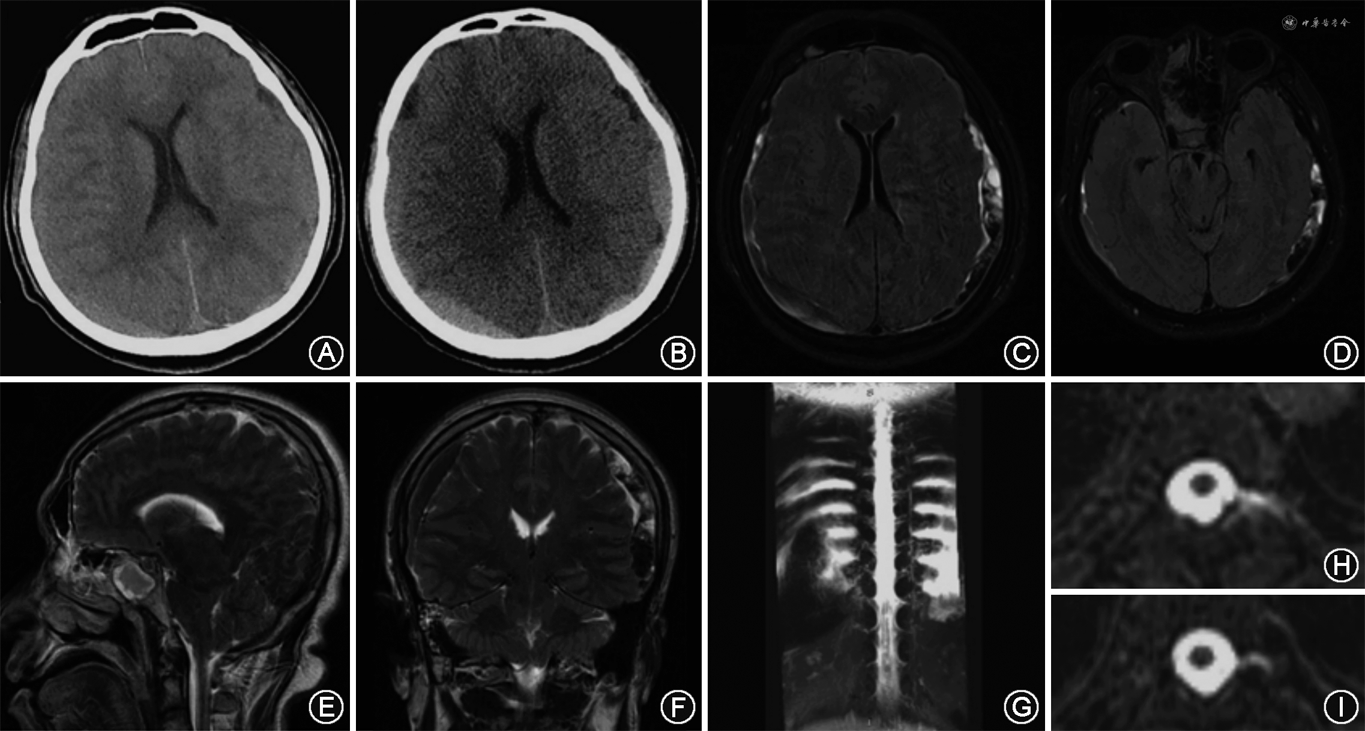

临床资料 患者男性,53岁,因“体位性头痛38 d,反复加重20 d”于2020年10月28日入首都医科大学宣武医院就诊。患者于2020年9月19日无明显诱因出现直立位时头双侧颞顶部持续性钝痛,伴有颈部僵硬,无恶心呕吐,平躺后缓解,无发热,至当地医院行头颅CT和MRI可见双侧横窦扩张,考虑“低颅压性头痛”可能,经卧床休息和补液保守治疗1周后症状缓解。2020年10月8日,无明显诱因下患者再次出现头痛,性质同前,至当地医院复查CT示双侧额颞顶枕硬膜下积液,双侧横窦扩张,再次补液保守治疗无效,头痛程度逐渐加重,并伴有恶心、出汗,无呕吐;遂转入我院。既往患有高血压、糖尿病、冠心病,余无特殊。体格检查:体温36.7 ℃,血压145/100 mmHg(1 mmHg=0.133 kPa),意识清楚,语言流利,反应灵敏,对答切题。脑神经体格检查未见异常。四肢肌力、肌张力、腱反射未见异常,巴宾斯基征阴性,共济运动检查未见异常,感觉系统检查未见异常。颈软无抵抗。入院后当日复查头颅CT示:双侧额顶颞枕部SDH;脑室系统变窄(图1A);中脑受挤压,脚间窝变窄;左侧横窦扩张较前不明显。经绝对卧床休息和补液治疗2 d,患者于2020年10月30日出现意识障碍,嗜睡,回答问题语量少、音量低,时间地点定向力障碍,小便失禁,格拉斯哥昏迷量表评分结果为4+4+6分。2020年11月4日,患者意识障碍加重至昏睡,格拉斯哥昏迷量表评分为3+3+5分,复查CT示双侧额颞顶枕SDH较前增多(图1B)。2020年11月15日,患者突然出现喷射性呕吐,体格检查:意识浅昏迷,言语不合作,双侧瞳孔等大等圆,对光反射灵敏,四肢可见自发活动,格拉斯哥昏迷量表评分为1+1+4分,急查头颅MRI示双侧SDH较前增多,血肿内信号不均一,并有隔膜形成,双侧额部硬膜增厚,脑室系统、中脑、脑桥受压变形,脑下坠明显(图1C~F),脊髓水成像示颈胸腰广泛硬脊膜外积液,神经根周围积液,高颈段硬膜囊后积液(图1G)。急行硬膜下血肿清除术,术后患者意识转清,可配合检查治疗,于知情同意下行腰椎穿刺,测脑脊液压力为100 mmH2O(1 mmH2O=0.009 8 kPa),微黄色,透明,白细胞9×106/L[正常值(0~5)×106/L],葡萄糖5.8 mmol/L(正常值2.5~4.4 mmol/L),氯化物124 mmol/L(正常值120~130 mmol/L),蛋白1.04 g/L(正常值0.15~0.45 g/L);获取知情同意后行MRI脊髓造影,可见T6、T7神经根脑脊液漏(图1H、I);于T6~7椎间隙行硬膜外穿刺以及靶向硬膜外血贴术(epidural blood patch,EBP)。

术后2 d患者直立性头痛消失,复查头颅CT未见新鲜硬膜下血肿(图2A),水成像可见硬脊膜外积液和神经根周围积液消失(图2B)。2021年1月9日,随访时患者复查头颅磁共振成像可见双侧SDH吸收,脑室及脑干受压缓解(图2C~F),至今随访5个月,头痛未再复发。